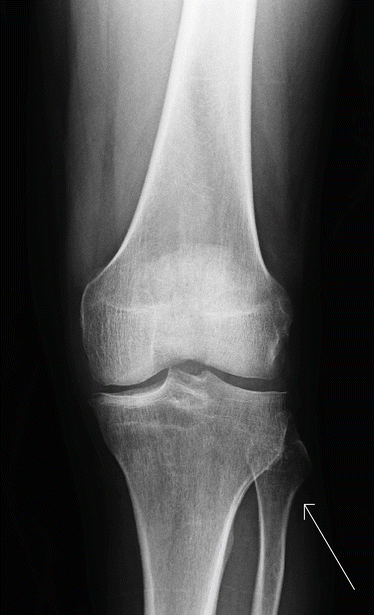

Proximal Fibular Osteochondroma Producing Common Peroneal Nerve Palsy In A Post Cesarean Section Patient A Manoharan 1 S S Suresh 2 Lakshmanan Sankaranarayanan3 Doi 10 5001 Omj 2013 63 1assistant Professor Orthopedics Chengalpattu - Soon after branching off from the sciatic nerve, it sends off two cutaneous branches.

A Rare Cause Of Drop Foot In The Pediatric Age Group Proximal Fibular Osteochondroma A Report Of 5 Cases Sciencedirect - The common peroneal nerve has a relatively short run.

Lariat Sign An Mri Finding Associated With Common Peroneal Nerve Rupture Sciencedirect - Peroneal nerve palsy associated with knee luxation: